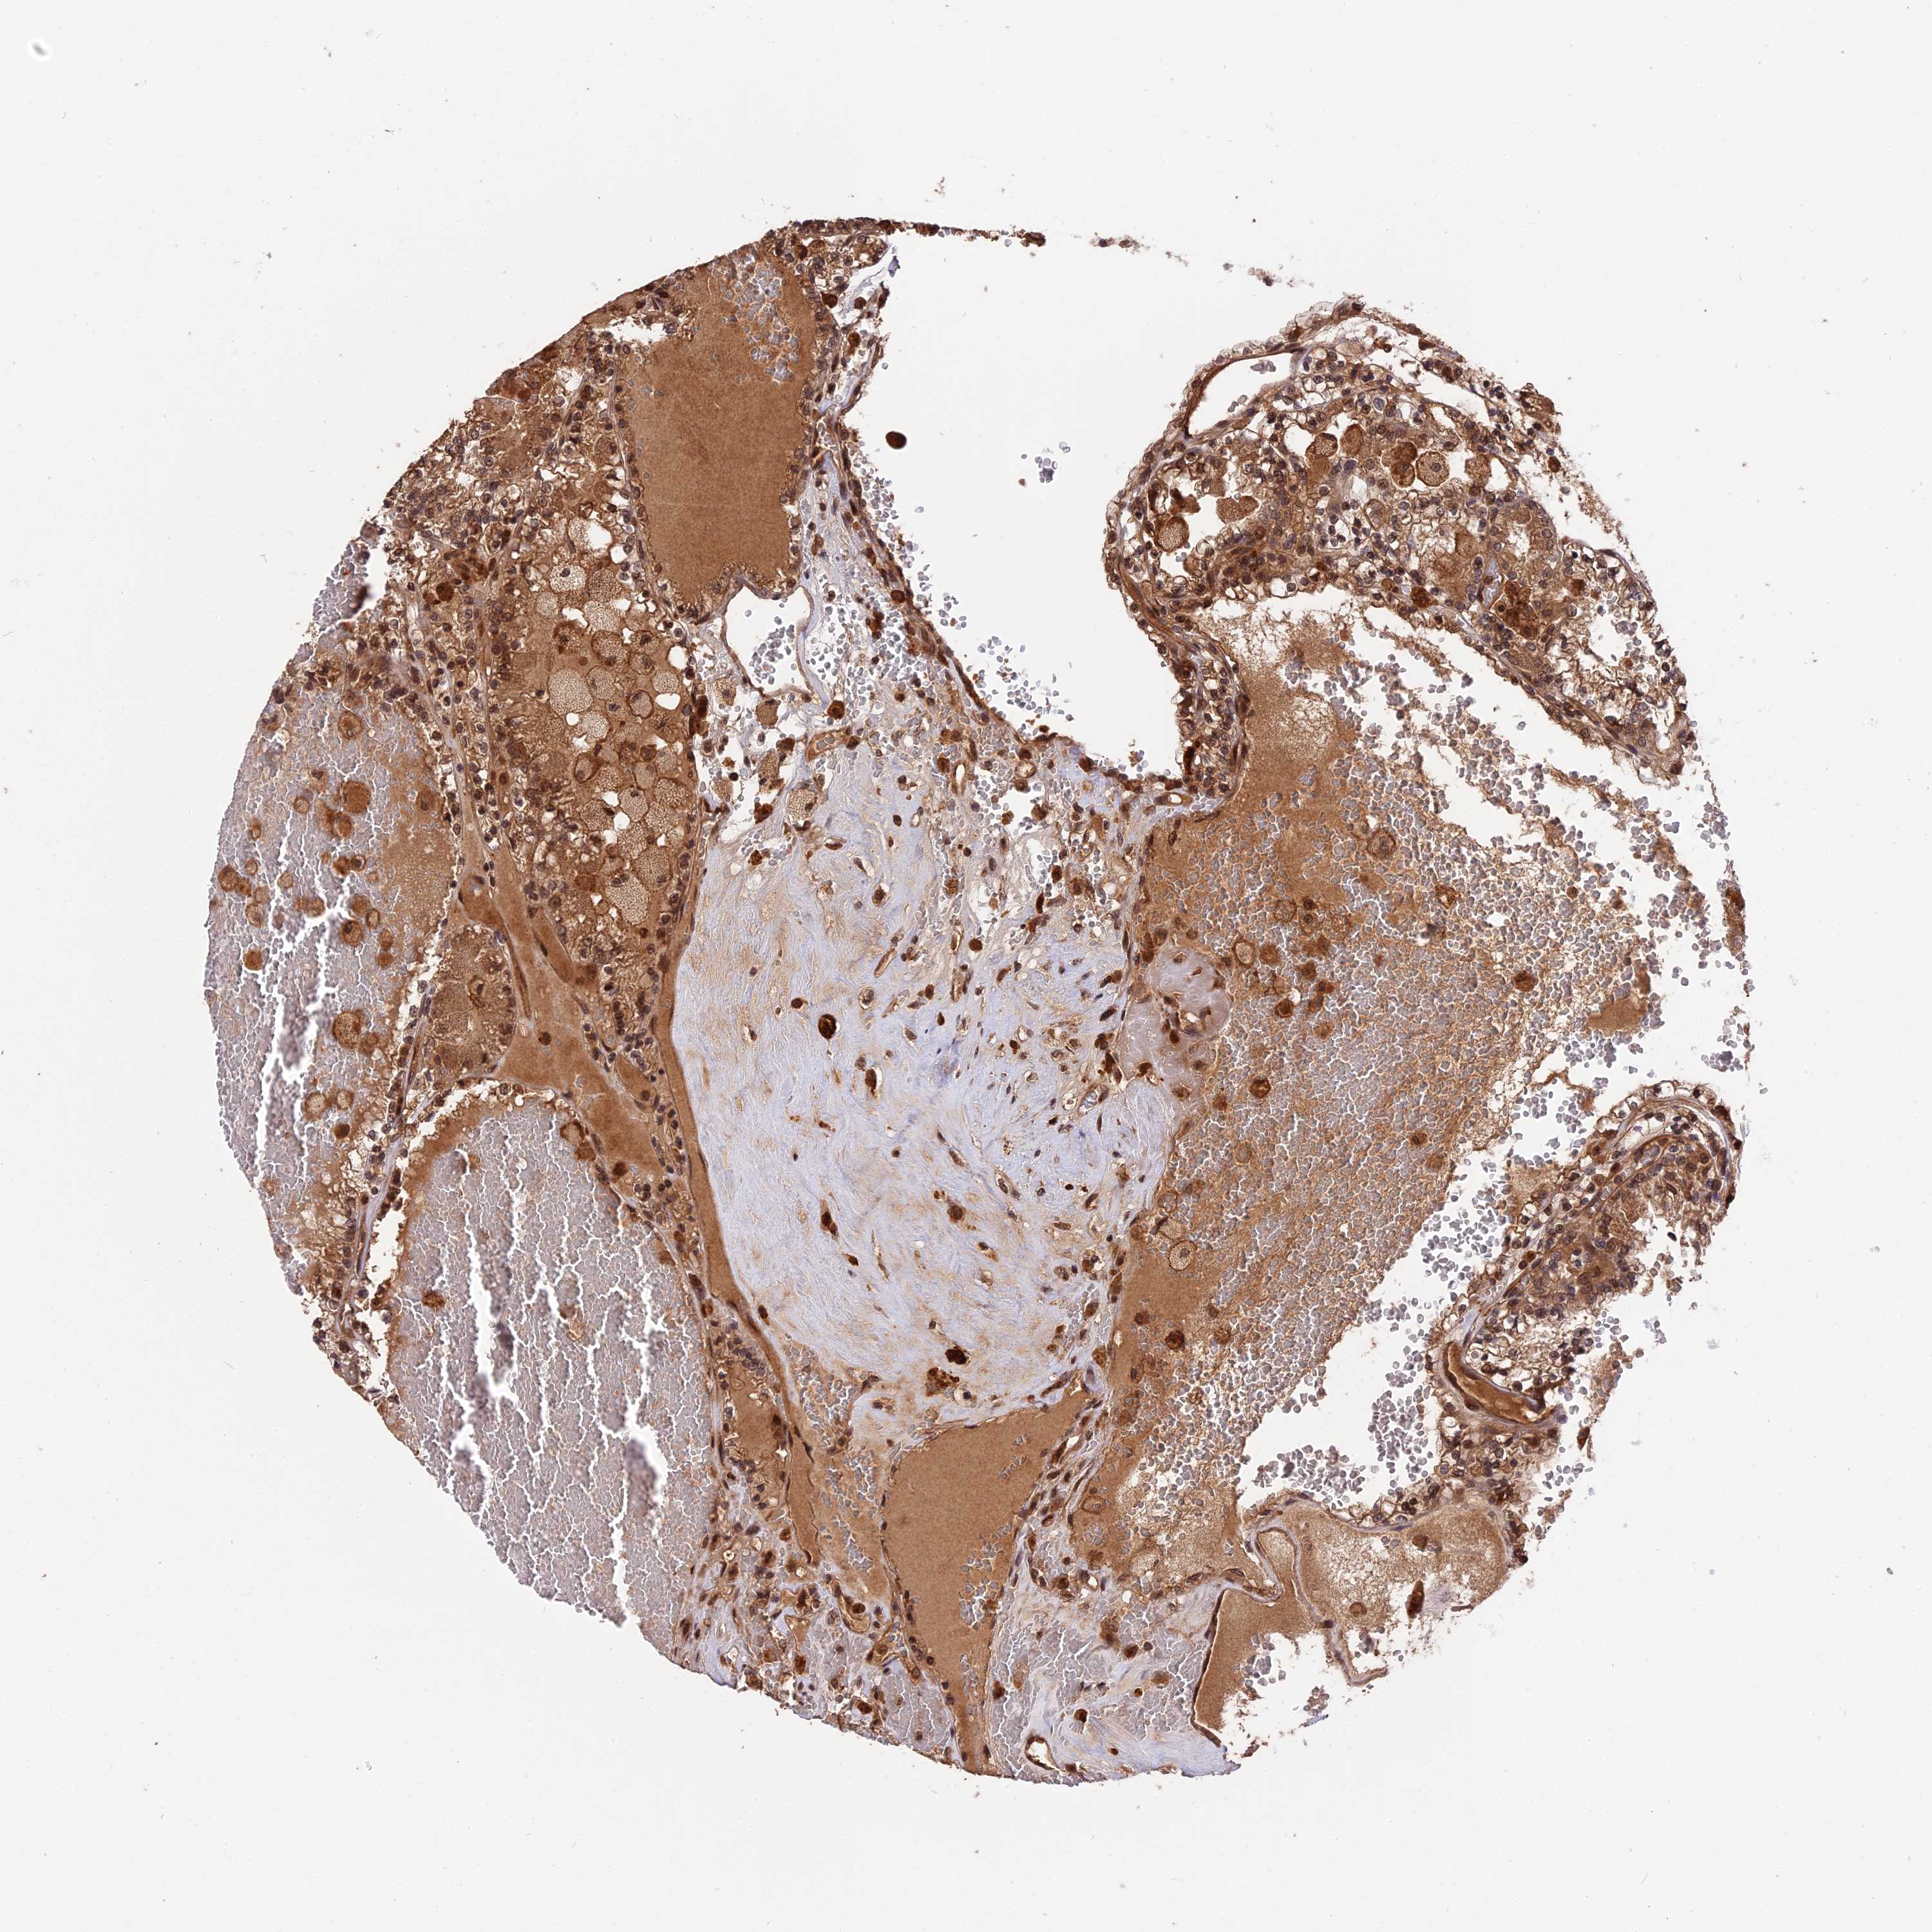

KIDNEY RENAL PAPILLARY CELL CARCINOMA (TCGA) - Interactive survival scatter ploti

The Survival Scatter plot shows the clinical status (i.e. dead or alive) for all individuals in the patient cohort, based on the same data that underlies the corresponding Kaplan-Meier plots. Patients that are alive at last time for follow-up are shown in blue and patients who have died during the study are shown in red.

The x-axis shows the expression levels (FPKM) of the investigated gene in the tumor tissue at the time of diagnosis. The y-axis shows the follow-up time after diagnosis (years). Both axes are complimented with kernel density curves demonstrating the data density over the axes. The top density plot shows the expression levels (FPKM) distribution among dead (red) and alive patients (blue). The right density plot shows the data density of the survived years of dead patients with high and low expression levels respectively, stratified using the cutoff indicated by the vertical dashed line through the Survival Scatter plot. This cutoff is automatically defined based on the FPKM cutoff that minimizes the p-score. The cutoff can be changed by dragging the vertical line or by entering a cutoff value in the square labeled "Current cut-off".

Under the Survival Scatter plot the p-score landscape (black curve; left axis) is shown together with dead median separation (red curve; right axis). Dead median separation is the difference in median mRNA expression between patients who have died with high and low expression, respectively. It is calculated as follows: median FPKM expression of dead patients with high expression - median FPKM expression of dead patients with low expression. This is intended to aid the user in visually exploring custom cutoffs and the associated p-scores and dead median separation.

Individual patient data is displayed and can be filtered by clicking on one or more of the category buttons on the top of the page. Categories describing expression level and patient information include: high, low, alive, dead, female, male and tumor stages. The scale of the x-axis can be toggled between linear and log-scale by clicking on the "x log" button. Mouse-over function shows TCGA ID, patient information and mRNA expression (FPKM) for each patient.

ESCO1 is not prognostic in Kidney Renal Papillary Cell Carcinoma (TCGA)